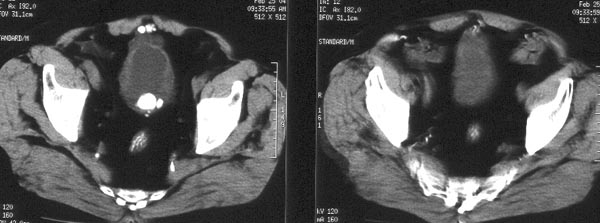

男性,74岁。尿频、尿线变细2年余,去年曾在外院膀胱结石超声碎石术。

ct平扫:膀胱内尿液充盈欠佳,膀胱壁较厚,前部见囊水样低密度影,内可见两枚直径1cm左右的钙化结石排列成串。膀胱右侧壁亦见囊水样低密度影。膀胱内可见多枚钙化密度结石影排列成串,大小约4.5x2cm。

ct诊断:1、膀胱多发结石。2、膀胱多发憩室,并憩室内多发结石。